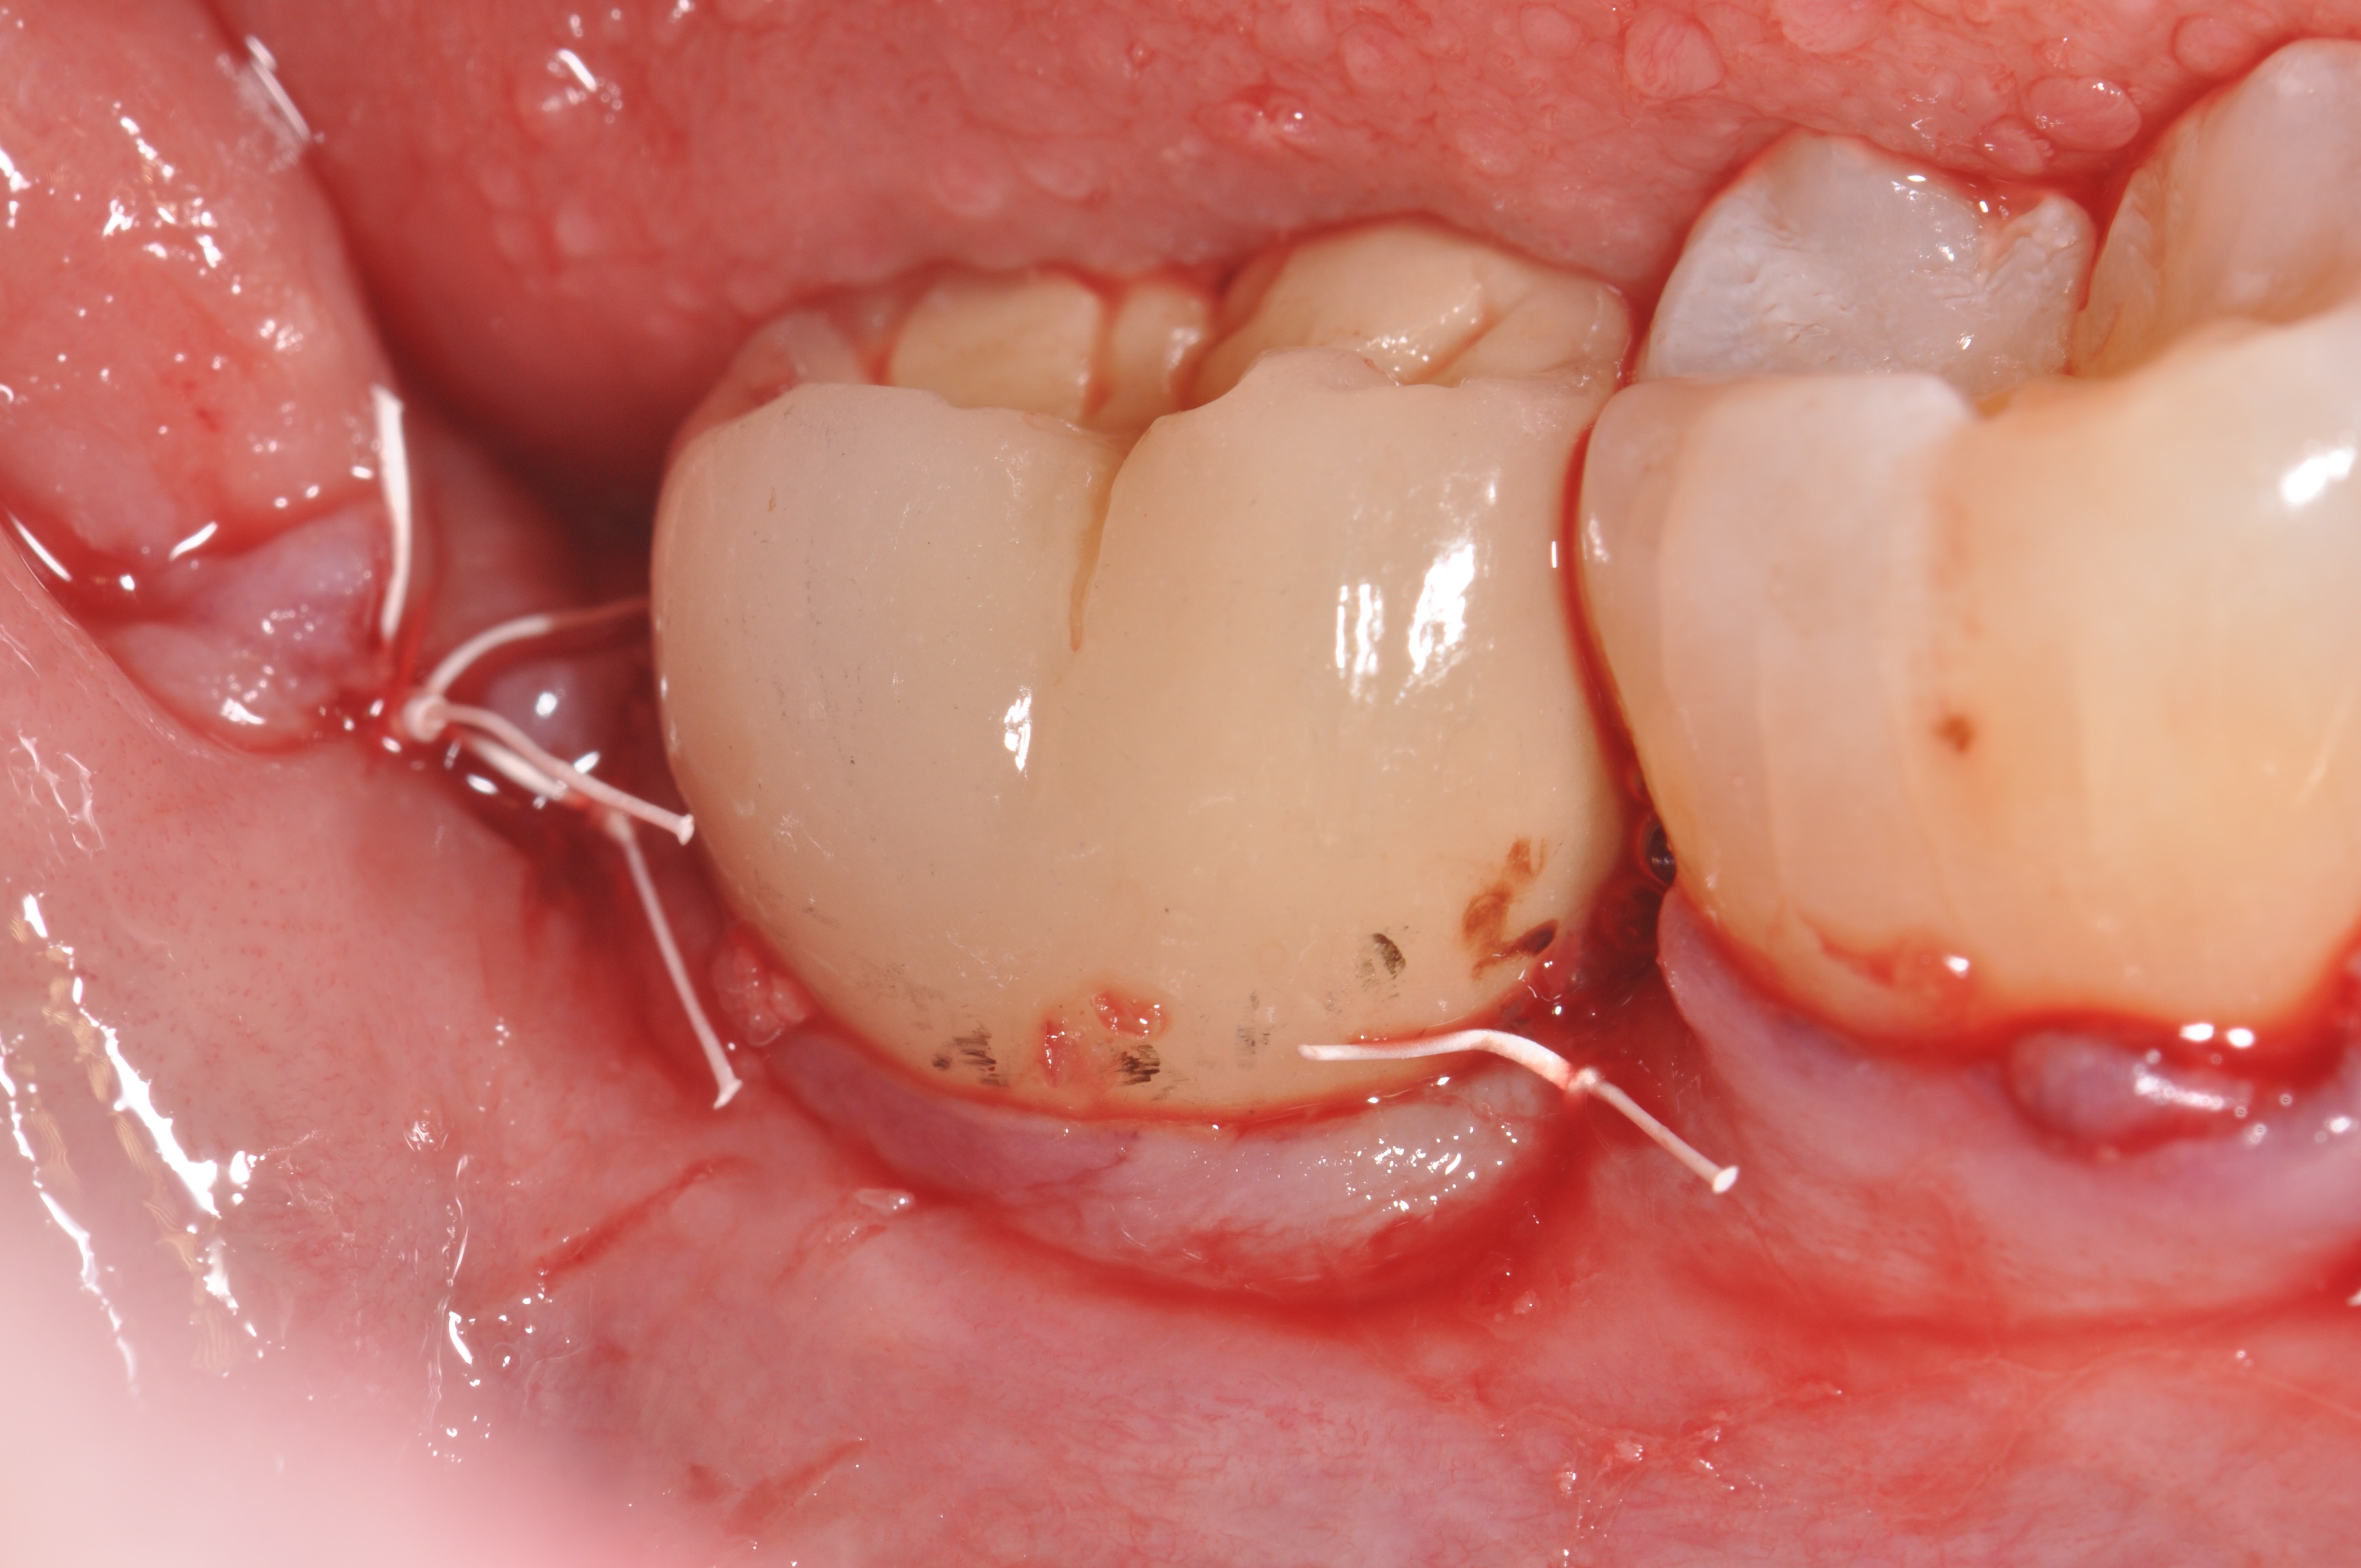

The flaps have been sutured together using expanded polytetrafluoroethylene.

Figure 5